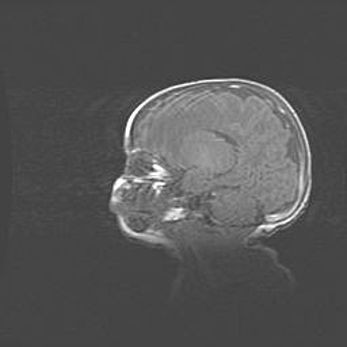

Аномалия Денди-Уокера. Признаки гипоплазии мозолистого тела.

Возраст: 5 месяцев 3 дня

Вес: 5550 г

Пол: мужской

Окружность головы: 39 см

Срок гестации: 40 недель

Аномалия Денди-Уокера – это порок развития головного мозга, для которого характерна триада симптомов: гипотрофия или аплазия червя мозжечка и/или полушарий мозжечка, расширение четвёртого желудочка с формированием ликворной кисты задней черепной ямки, гипертензионная гидроцефалия различной степени.

Гипоплазия мозолистого тела относится к дефектам внутриутробного этапа развития мозговой ткани, возникающим в процессе закладки структур головного мозга, что происходит на начальных этапах развития эмбриона.